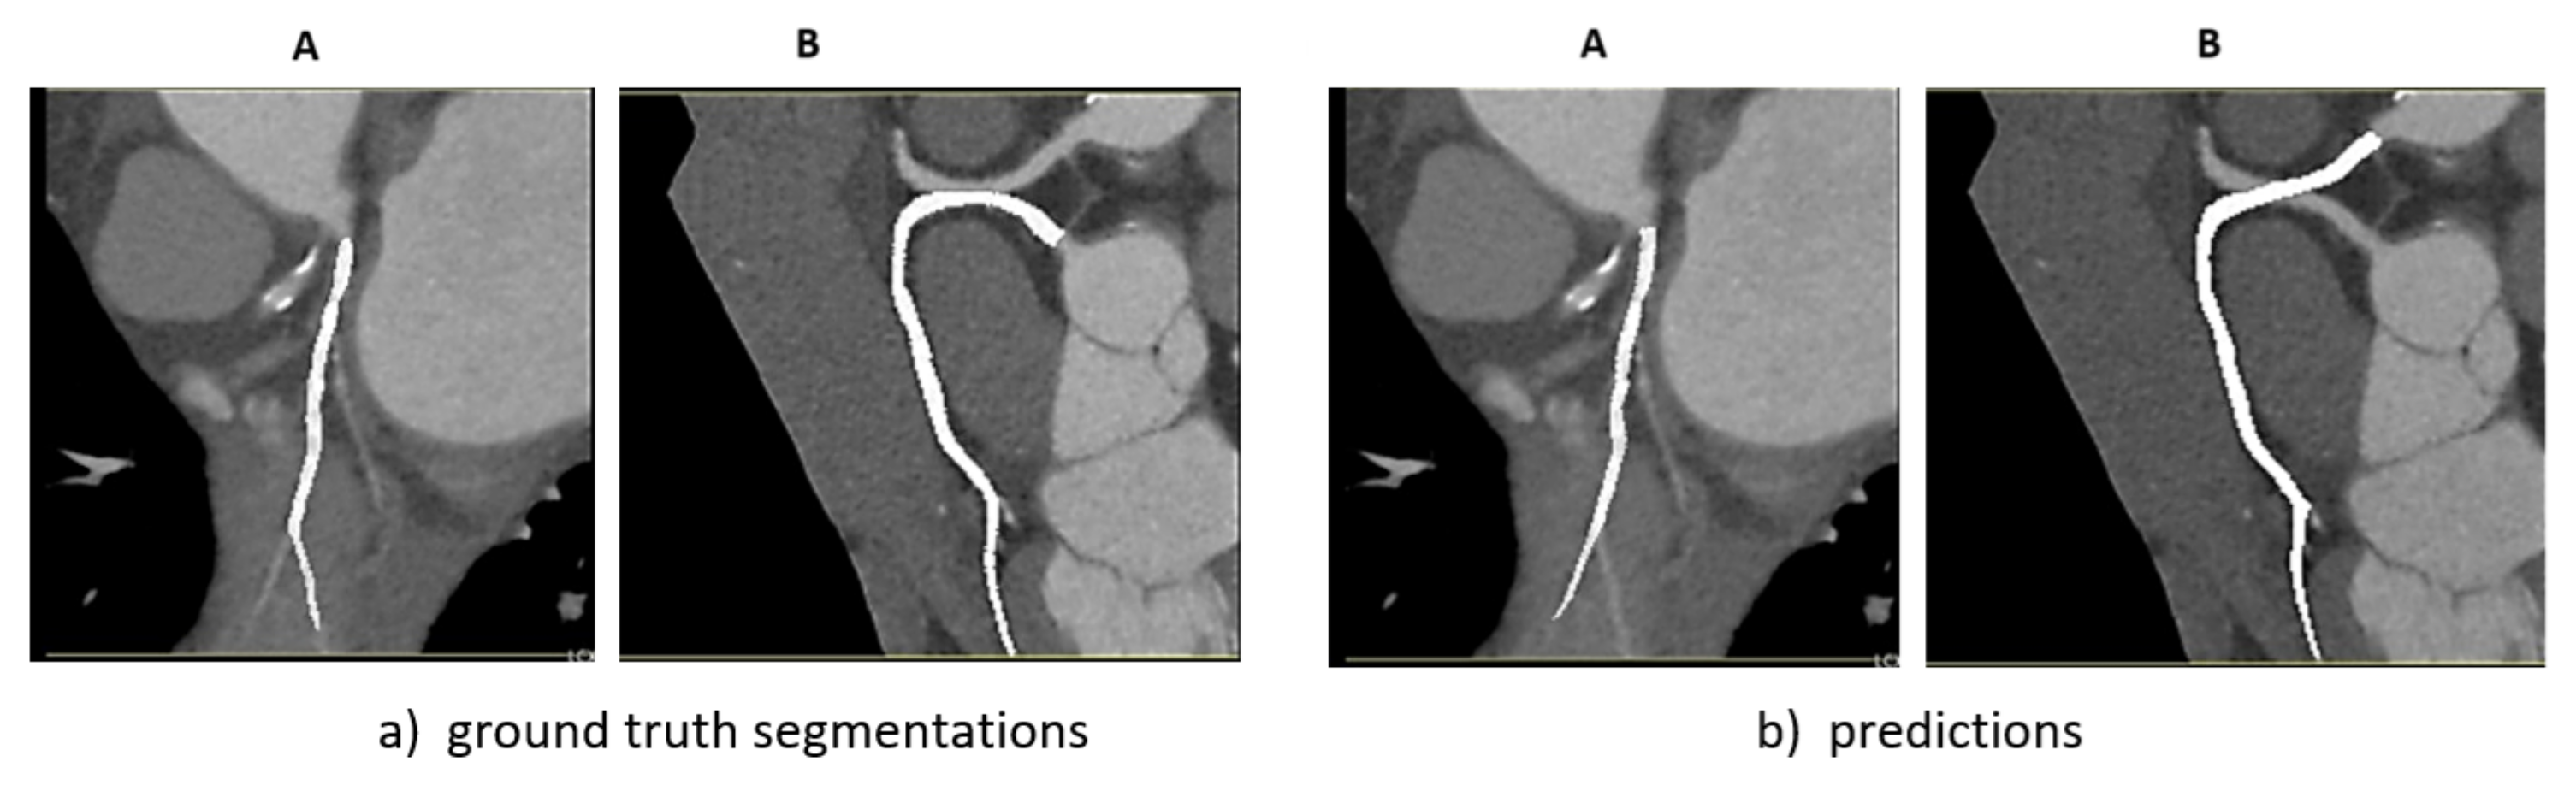

4.2. Comparison of Intra-Observer Annotations

- Prediction against previously annotated data (old)

- Prediction against newly annotated data (new)

- Difference between previously annotated and newly annotated data (human)